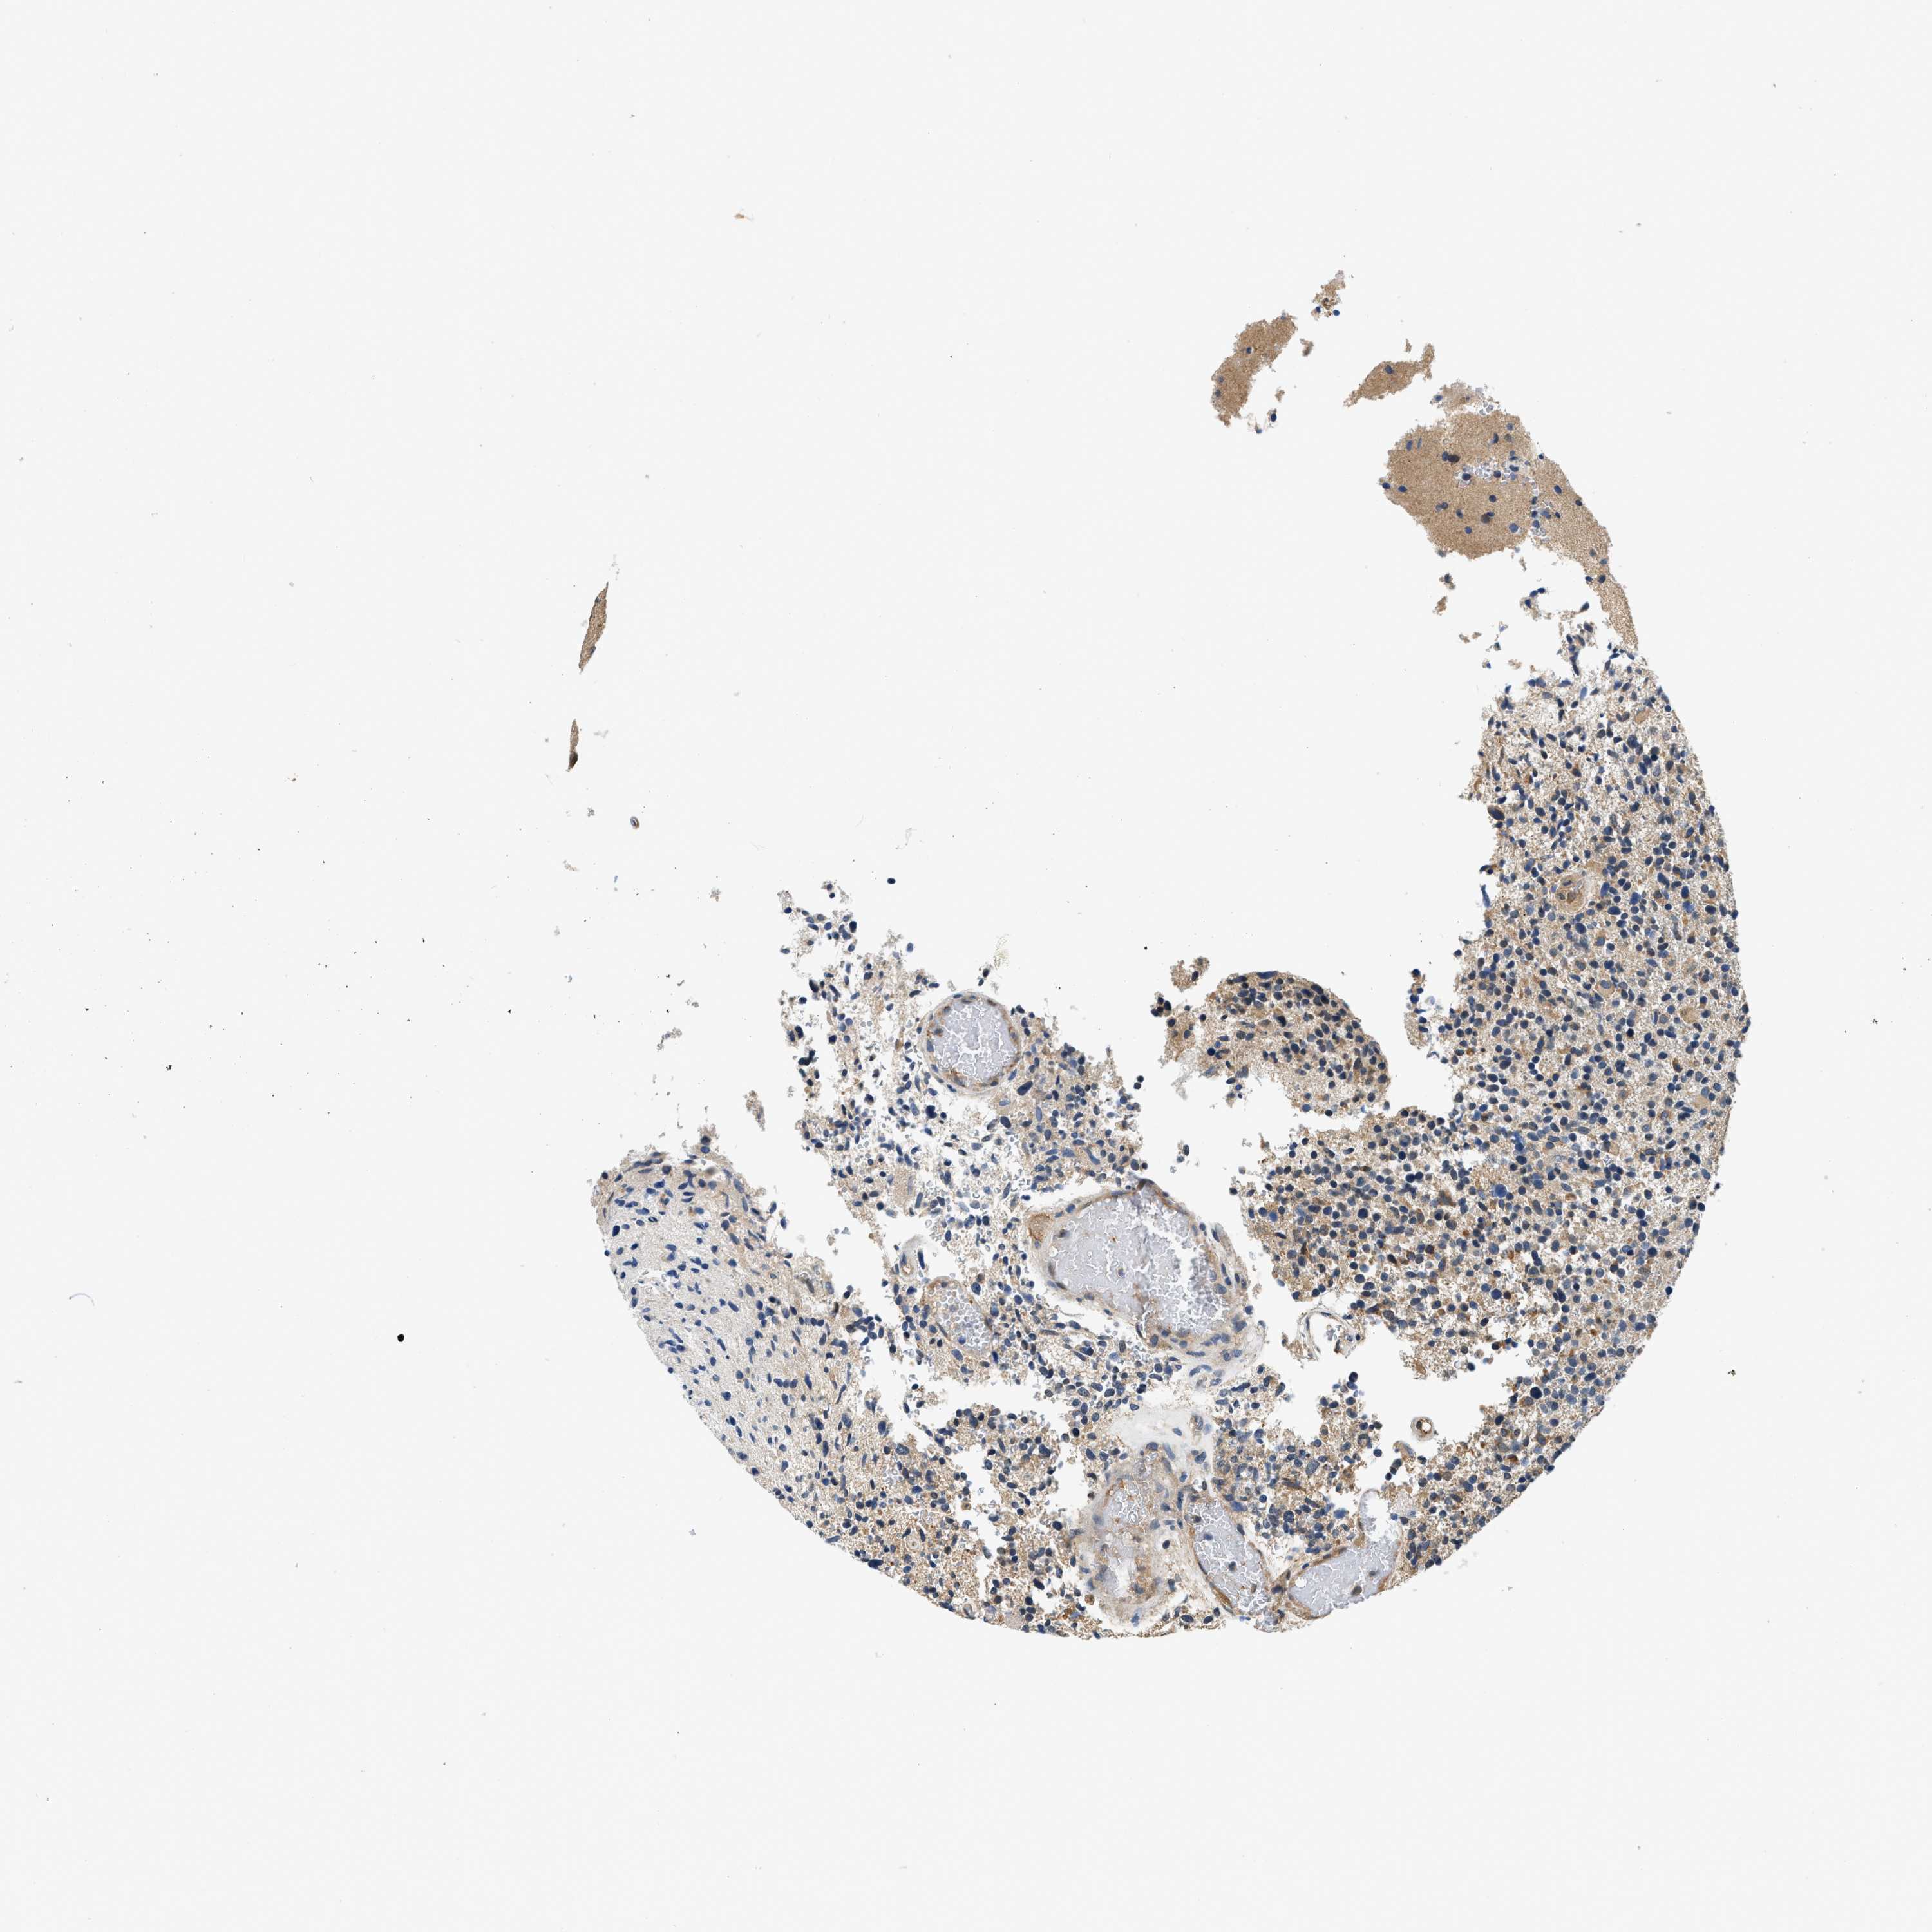

GLIOMA - Protein expressioni

A mouse-over function shows sample information and annotation data. Click on an image to view it in a full screen mode. Samples can be filtered based on level of antibody staining by selecting one or several of the following categories: high, medium, low and not detected. The assay and annotation is described here.

Note that samples used for immunohistochemistry by the Human Protein Atlas do not correspond to samples in the TCGA dataset.

Antibody stainingi

Antibody staining in the annotated cell types in the current human tissue is reported as not detected, low, medium, or high, based on conventional immunohistochemistry profiling in selected tissues. This score is based on the combination of the staining intensity and fraction of stained cells.

Each image is clickable and will lead to virtual microscopy that enables deeper exploration of all samples and also displays staining intensity scores, fraction scores and subcellular localization as well as patient and tissue information for each sample.

Antibody HPA018676

Staining

High

Medium

Low

Not detected

Intensity

Strong

Moderate

Weak

Negative

Quantity

>75%

75%-25%

<25%

None

Location

Nuclear

Cytoplasmic/membranous

Cytoplasmic/membranous,nuclear

Glioma, malignant, High grade

Glioma, malignant, Low grade